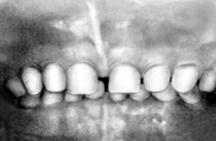

Поскольку сроки и последовательность формирования молочного и постоянного прикуса у детей достаточно определенны (таблица 2,3), их широко используют в определении « зубного возраста», который устанавливают путем подсчета числа прорезавшихся зубов и совпадения его со стандартными возрастными нормами.

Молочные зубы прорезываются с 6 мес до 2-2,5 лет и на этом отрезке постнатального онтогенеза могут служить в качестве показателя физиологической зрелости.